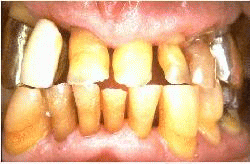

El mismo paciente después del tratamiento, la patología periodontal se ha eliminado y las profundidades de bolsa son de 1-2 mm.  La condición periodontal se observó durante tres citas en un mes. La salud periodontal se mantuvo por los procedimientos de higiene oral y la rehabilitación protética del maxilar superior.

Después de  3 años del tratamiento periodontal y rehabilitación oral por puentes fijos. La condición periodontal es estable y el nivel de higiene oral se mantuvo. El puente fue diseñado para permitir una  limpieza eficaz de las raíces y las uniones entre las raíces y las coronas. Note en particular el ancho espacio interdental y el ajuste de las coronas a la anatomía de superficie de la raíz. El paciente es recitado cada seis mes y no se observó ninguna progresión a enfermedad periodontal.